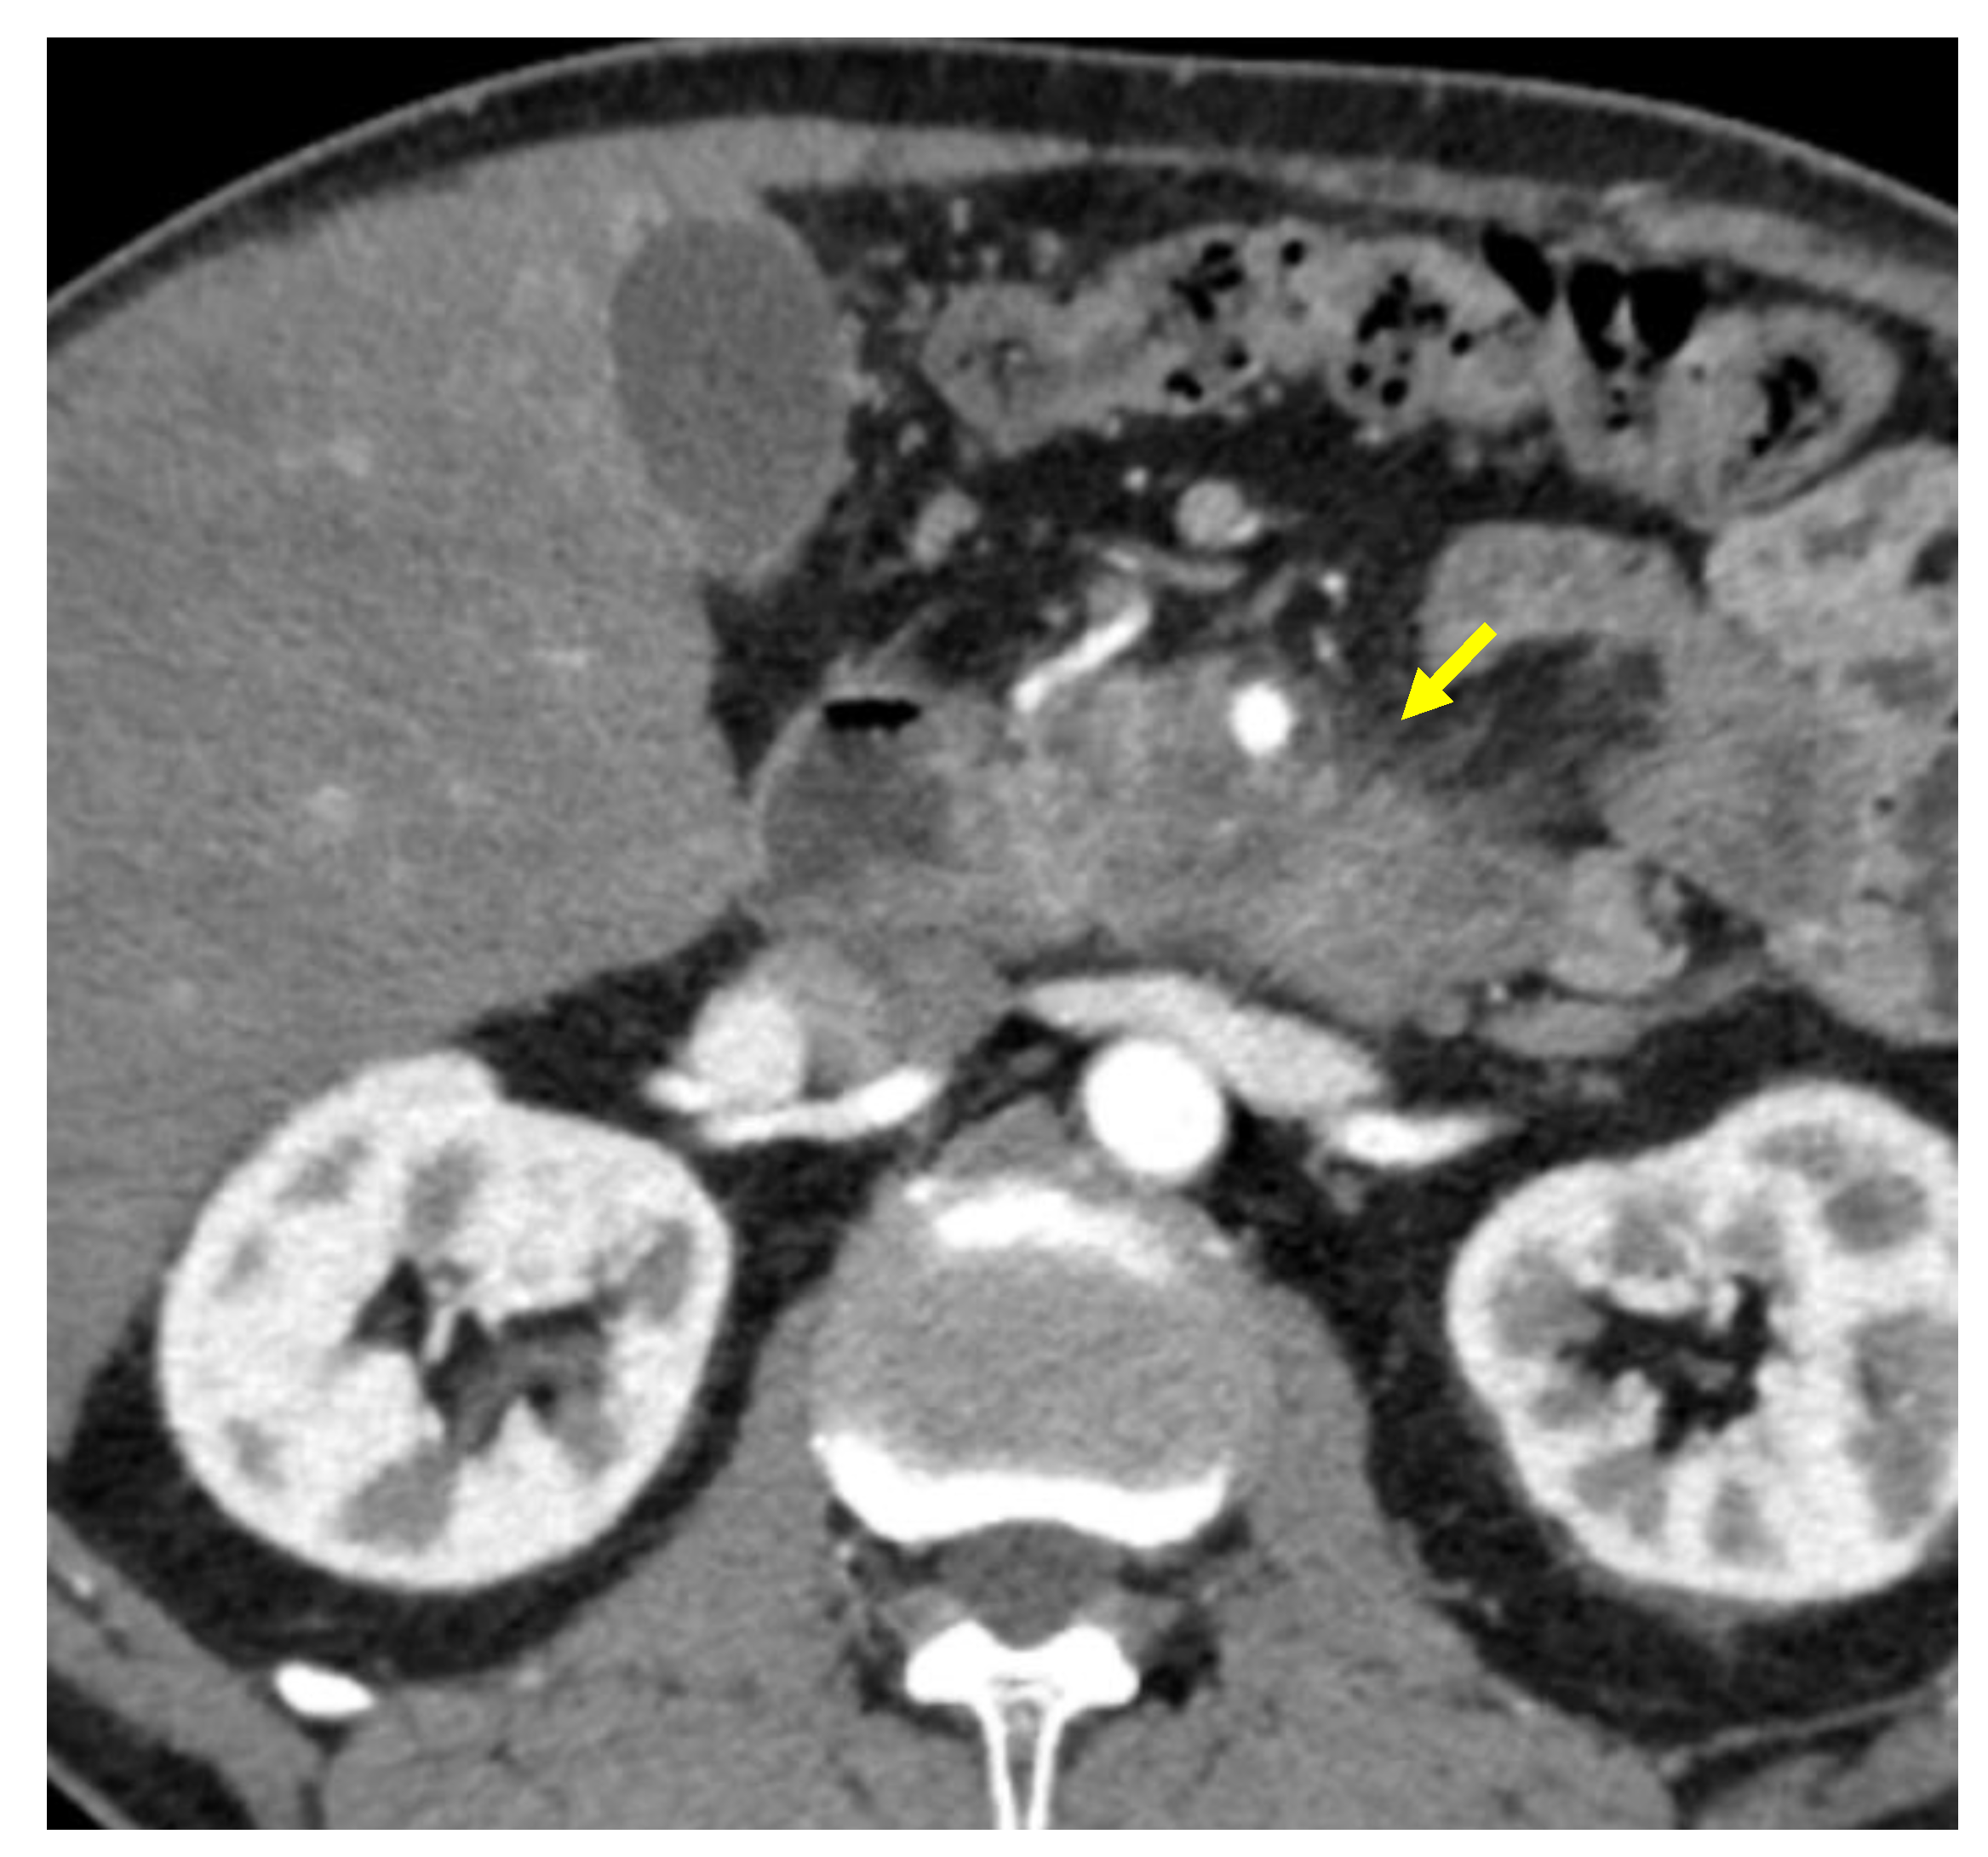

Tumor margins showed a significant difference in the two groups, appearing well-defined in only 6 (6.98%) metastatic patients and ill-defined in the remaining 80 (93.02%); in the non-metastatic group, the margins appeared well-defined in 132 (65.35%) and ill-defined in 70 (34.65%) tumors (Figure 2, Figure 3, Figure 4 and Figure 5).

Figure 3. Pancreatic lesion with well-defined margins (arrow) on CT examination in portal-venous contrast phase.